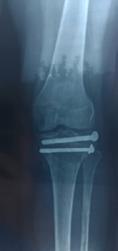

În lucrarea de față vom prezenta cazul complex al unui pacient în vârsta de 84 de ani, ce a fost diagnosticat în primăvara acestui an cu Gonartroza bilaterala stadiul III, decompensata algic și functional pe dreapta, care în urma evaluării clinice, biologie și imagistice a urmat intervenția

de protezare a genunchiului, cu o evoluție postoperatorie favorabilă, fără complicații. În urma dispensarizării la domiciliu, la 3 săptămâni postoperator, pacientul suferă un traumatism prin cădere de la același nivel, prezentându-se în Serviciul de Urgență tardiv, după aproximativ 10 ore, cu o plagă dehiscentă pe fața anterioară a genunchiului, exteriorizându-se la piele ligamentul rotulian restant, dezinserat de la nivelul polului inferior rotulian. Intraoperator se practica debridare mecano-chirurgicala intensivă, cu îndepărtarea marginilor plăgii, ale țesuturilor necrozate, lavaj intens, abundent și sutura ligamentului rotulian (Fig 1; Fig 2).

În a doua etapă, după parcurgerea curei antibiotice, se practică revizia cu implantele finale, folosind proteza de revizie de tip balama, cu stem femural și tibial lung, cu protecția oferită de perlele de Stimulan impregnate cu Vancomicină și Linezolid.

întreg – dar osteointegrarea osoasă la nivelul TTA fiind completă), motiv pentru care am decis utilizarea unui substitut alloplastic- meșă (plasă) de polipropilenă 30x30cm care a fost preparată astfel: bucata de material a fost pliat în 8 straturi, având o l=3cm și o L=30 cm, fiind suturată cu fir neresorbabil pe lateralele sale, urmând a fi cimentată in canalul tibial odată cu componenta protetică tibială. După stabilirea indicelui Insall-Salvati corect, s-a folosit o langetă musculară din dreptul femural după tehnica Ducroquet care a acoperit noul ligament sintetic, oferind protecție si bază nutritivă și a fost stabilizat cu ajutorul a 2 ancore cu fire nerserobabile (Fig 4+5+6). Postoperator pacientul este imobilizat în aparat gipsat femuro-gambier pentru 6 săptămâni, mărind treptat gradul de flexie.